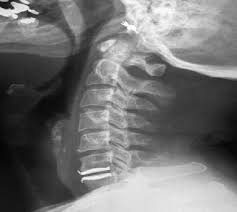

Pro-Disc C5-C6 **Please help** Placement?

Is my disc in right? too small? forward?

At 4 months post op my neck pain is far worse then before surgery.

It is what it is. It looks like the joint is functioning as the relative angle of the plates moves as expected with flexion/extension.

IMHO, if the pain us unchanged or the same pain is worse after surgery, the pain generator was somewhere else and looking at the implantation is a distraction. (no pun intended)

Your disc is not subsided. If it looks the same as it did in the interoperative or immediate post-op images, then it's not migrated.

It looks a little off centre...closer to RT side, and a little taller than the natural disc height. But maybe within the acceptable parameters? I'm no expert.

Here is my 5 month X-Ray...

Is my Pro-Disc to Forward?

The "surgeon" cut the keel slot wrong. The implant is tilted as is your spine. It changes the vectors of all your vertebra.

He also did not prepare the surfaces correctly. That is another reason it is tipped. Think of it like this. You install a door and the hinges are not plumb and square. It may close OK and look fine but when you open it more than 1/2 way it scrapes on the floor.

You have big osteophytes.

You lost the lordosis curve.

This is a healthy C-spine. Notice the nice curve. I your X rays the vertebra are all over the place. The vertebrae below the implant are in the correct position. The ones above it are tilted and twisted. This will cause nerve irritation and lots of pain. If you butcher/surgeon can't figure that out key his BMW.

Also the implant is TOO BIG!

Notice how your left shoulder has pulled up and how your collar bone is distorted.

That disk has made your spine bent and twisted. It is too big and it was put in wrong. You are probably having pain where you never had it before. IMO it you don't get this piece of improperly installed junk removed you will never get better.

The films here show a very subluxated C-spine above the 5-6 level and IMO the cause is a poorly implanted Frankenstien disk.

My eye is very untrained but it does look like your upper cervical levels are twisted or torqued and whether they were that way before the ADR placement or not may make a difference as well in terms of feeling worse post operatively as you state.

Seems like the ADR is tilted and the disc space jacked up but that's just to me which means nothing except if I saw this on my own films I'd think maybe that was increasing the probs/pain in the levels that weren't treated and are kind of messed up.

Again, IMHO while the implantation may not be optimum, it is not that bad. I have seen much worse with successful outcomes. We don't know what compromises were NECESSARY in the implantation that resulted in the final configuration looking like it does.

The lordosis being lost is because of the levels above the ADR, not due to the ADR.

The CT image leads me to believe that some subsidence could be resulting in the tilt that is shown, but it is not very clear on the xrays.

Look at the height of the disk spaces and then look at the height of the ADR. It looks like he put in a lumbar disk. That would explain the loss of the lordosis curve. Do you have any pre surgery films. If the disk is too big you might have a lawsuit.